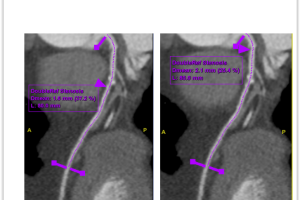

MSCT koronarografija je brza, precizna i neinvazivna metoda snimanja koja nam omogućava jasan uvid u stanje vaših koronarnih arterija. Pomoću najsavremenije CT tehnologije, možemo detaljno analizirati protok krvi i identificirati eventualna suženja ili blokade.

3. Precizna dijagnostika: Najsavremenija tehnologija omogućuje nam otkrivanje čak i najmanjih promjena u koronarnim arterijama.